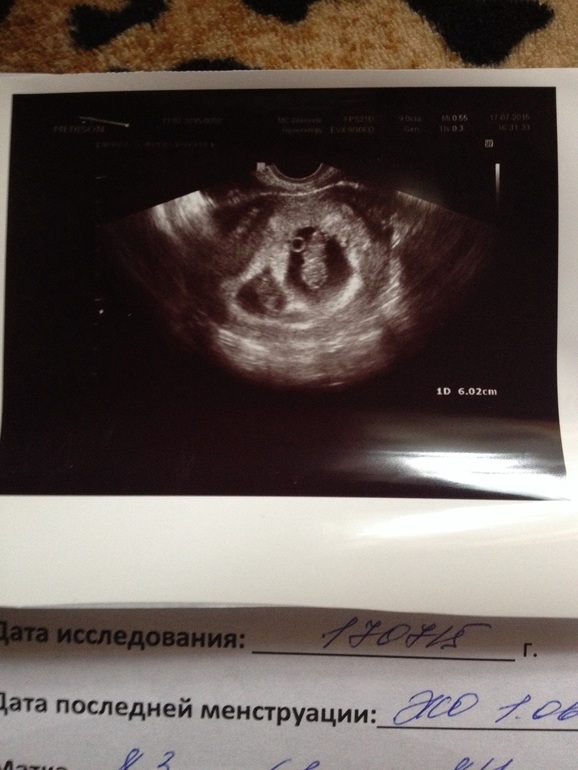

Девочки посмотрите пожалуйста на УЗИ

Всё о нашей беременности Девочки привет. Сегодня после перелета на самолете и после поезда начал болеть живот. Сходила на узи вот результаты. Это нормально что один на столько больше другого? Начинаю за мою кроху волноватся(

Спасибо за поддержку! У меня 17-го по предыдущему узи должно было быть 9 недель. А тут один 8 недель и 1 день, а второй 8 недель и 5 дней

О, это нормально!!! один всего на 4-ре дня от другого отстаёт. Бывает и на неделю отставание и больше! так, что всё в порядке! пусть дальше растут хорошо!!